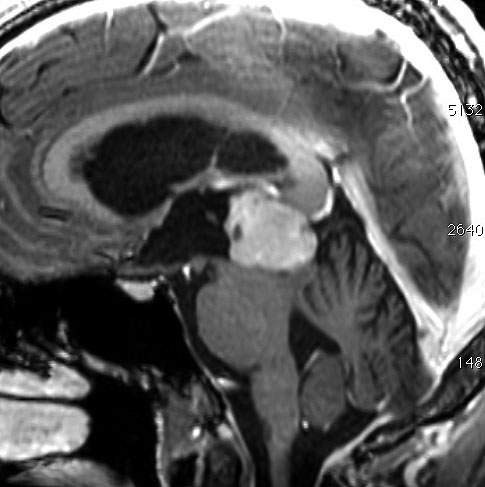

これも偶然発見された無症状の女性の小さい松果体細胞腫ですが,ほとんど実質性でのう胞がありません。右はCISSという画像です。中脳の視蓋は圧迫されて変形していますが,中脳水道がまだ閉塞していないのがよくわかります。

左側はMRI血管像です。赤く塗った松果体腫瘍がたくさんの血管とくに静脈に囲まれていて深い位置にあるのがわかります。右は手術後のMRIです。幸い後交連というところも残せたので眼球運動障害(ものが2重に見える)という後遺症は出ませんでした。